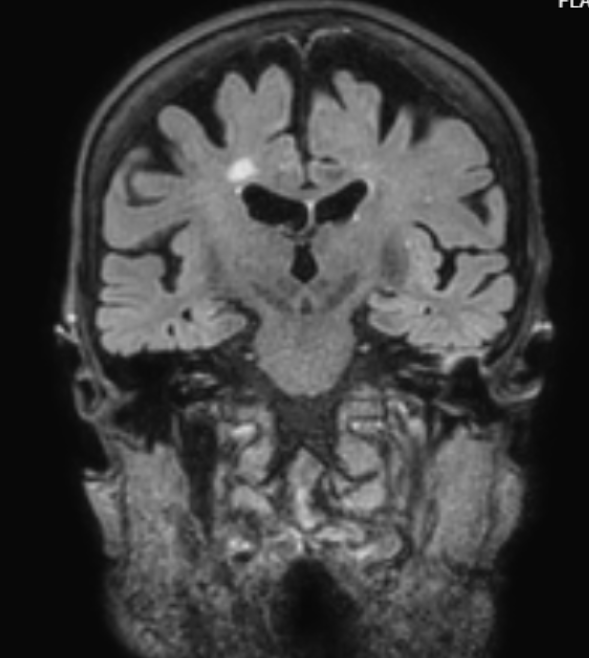

Icobrain by Icometrix

Icobrain ms – Objectively track disease progression in individual multiple sclerosis patients.

Icobrain dm – Objectively quantify relevant brain structures in individual dementia patients.

Icobrain tbi – Towards standardized and quantified interpretation of brain scans for traumatic brain injuries.

Icobrain ep – Towards a more confident diagnosis of patients with epilepsy